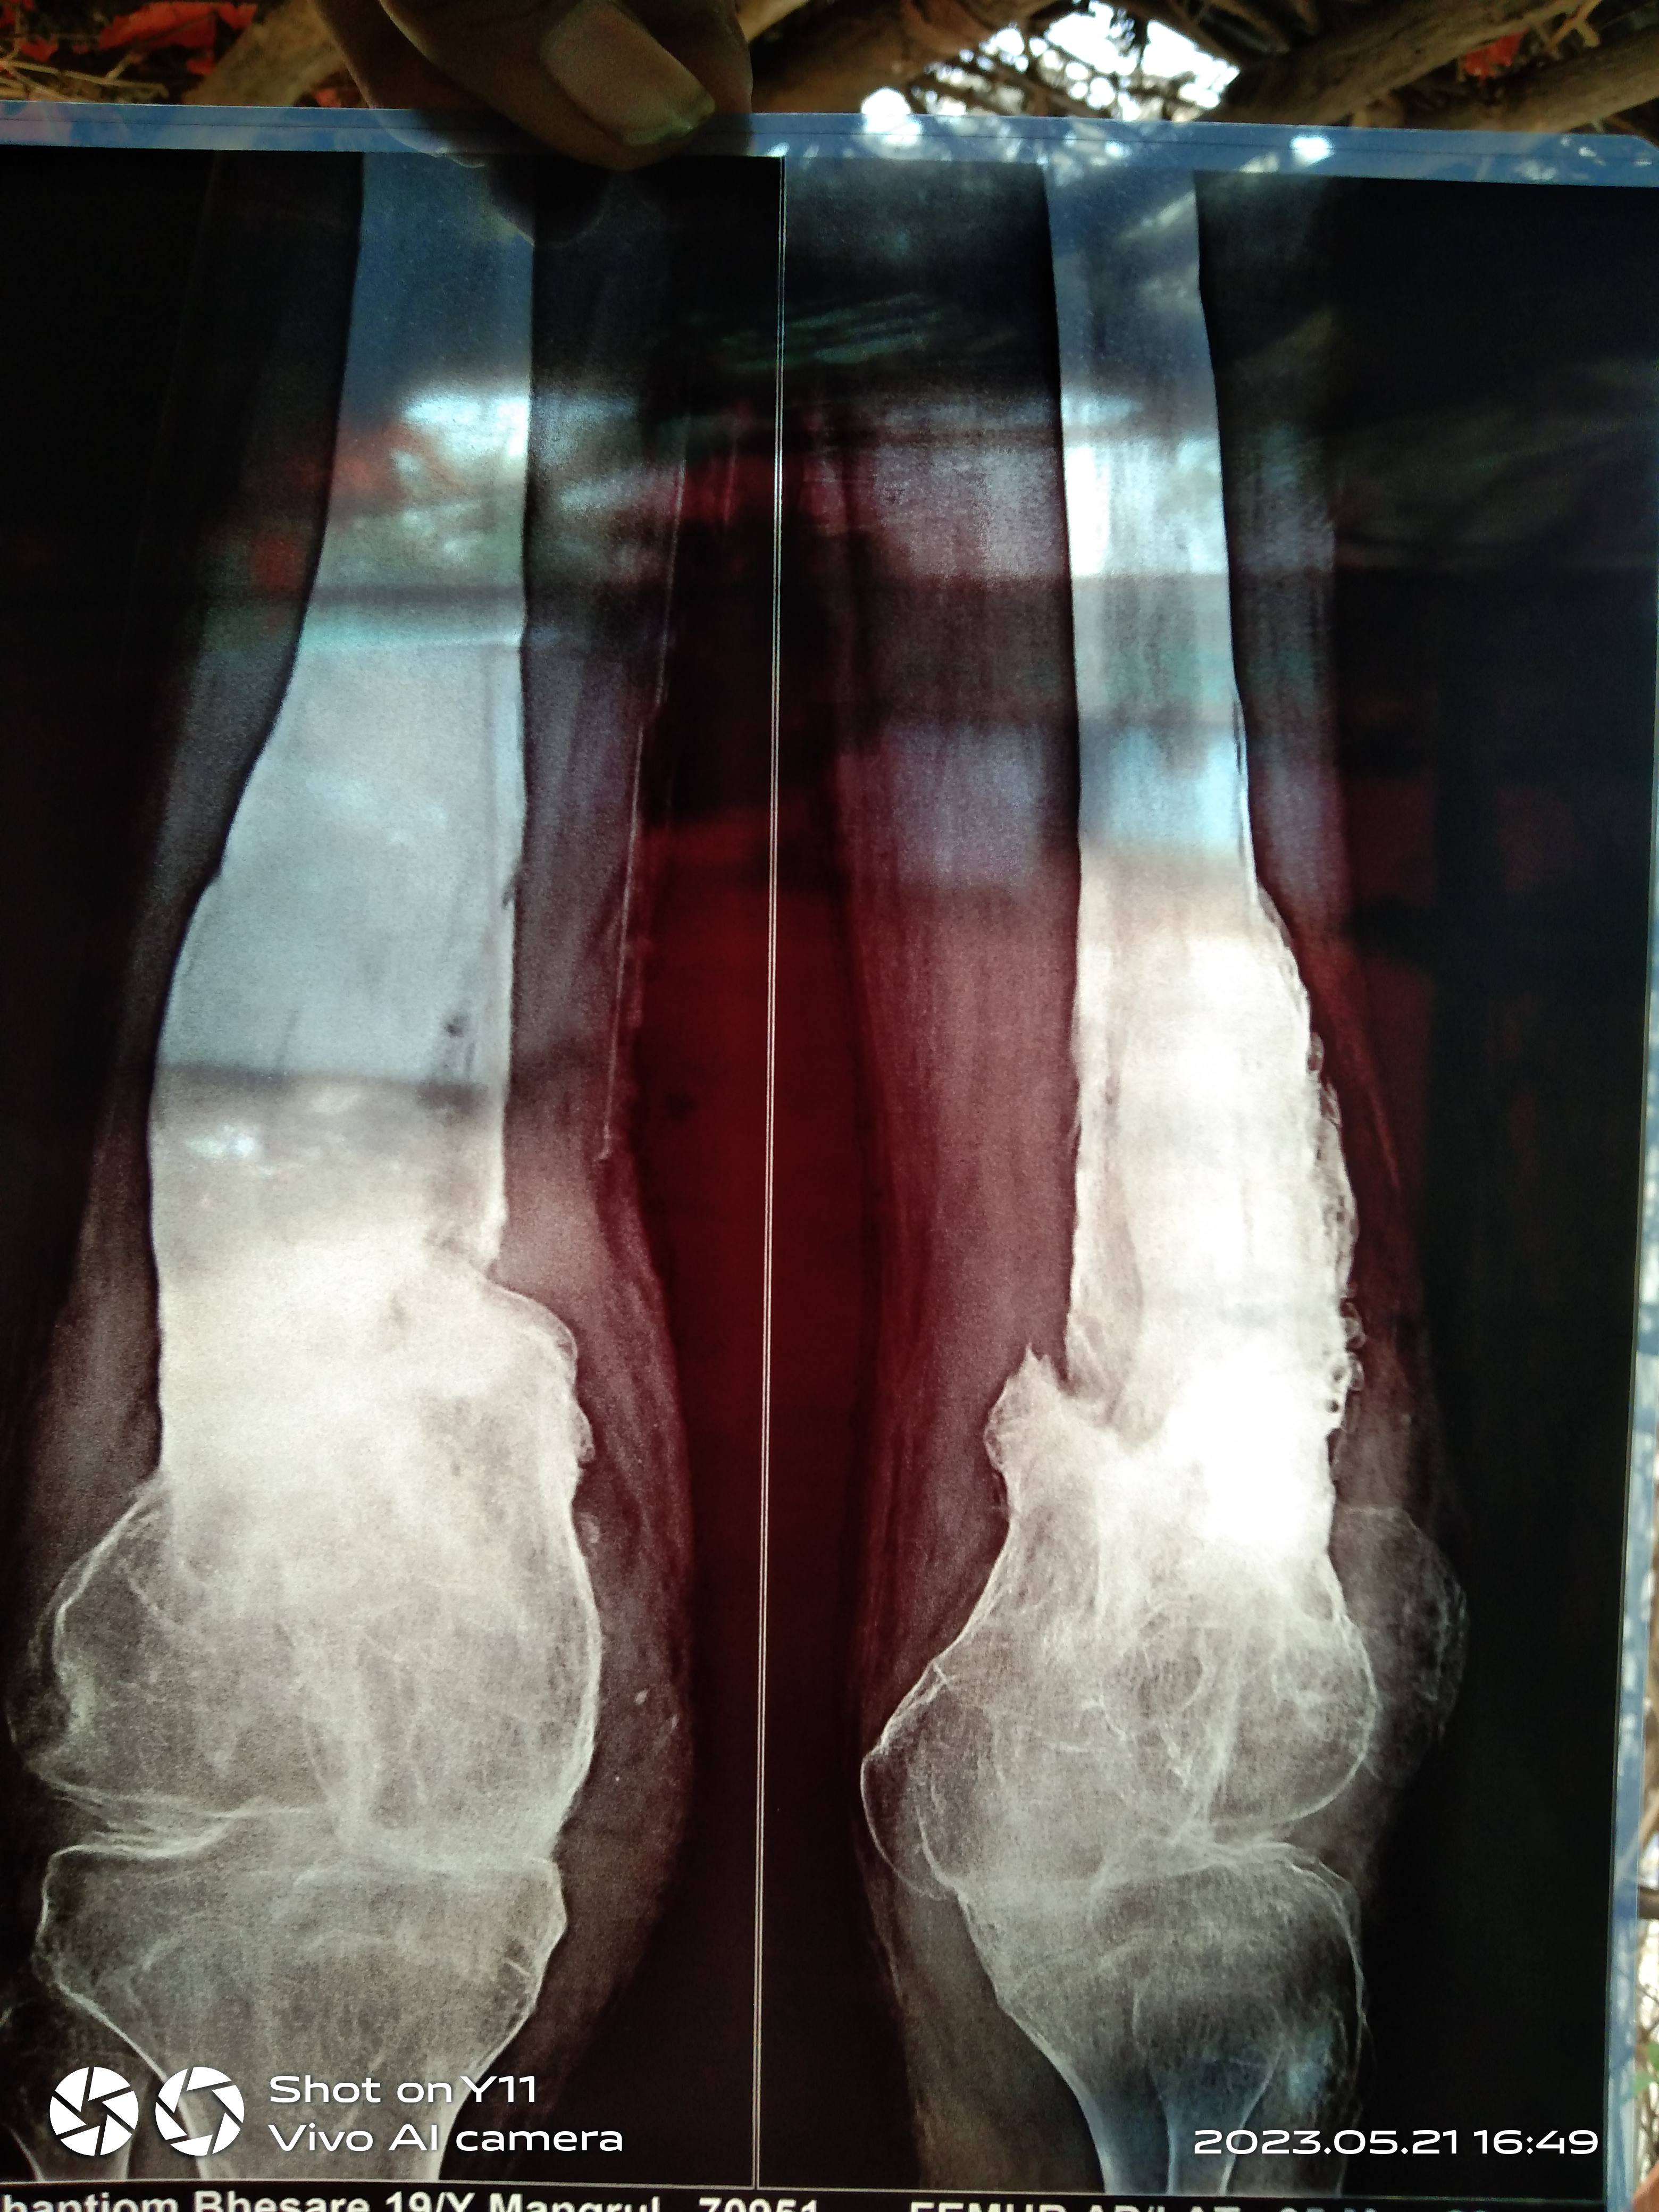

Shantiom Bhaisare